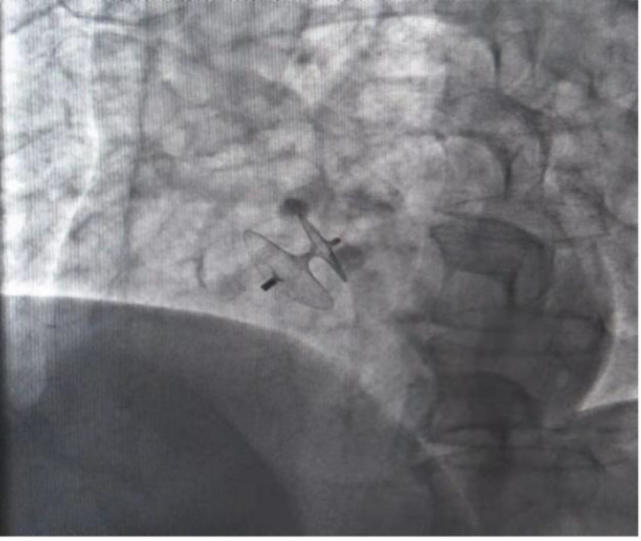

图片

介入封堵

邵中兴介绍,为了“堵”上心脏上的这一“小洞”,医生通常将从患者的右侧股静脉即大腿根部置入微导管,从而建立通道。“形象地说,卵圆孔的封堵器像个伞面。收起时,封堵器呈长条形通过微导管送入心脏,释放后,它可以像撑开伞那样膨胀起来,在左心释放左盘,再拉到右心释放右盘,相当于夹了起来。”

邵中兴告诉记者,这样的介入封堵治疗手术时间短,创伤小,相比于药物干预能够有效预防脑中风和改善脑中风预后。而对于偏头痛患者来说,介入封堵治疗更可以明显治愈或缓解偏头痛症状。